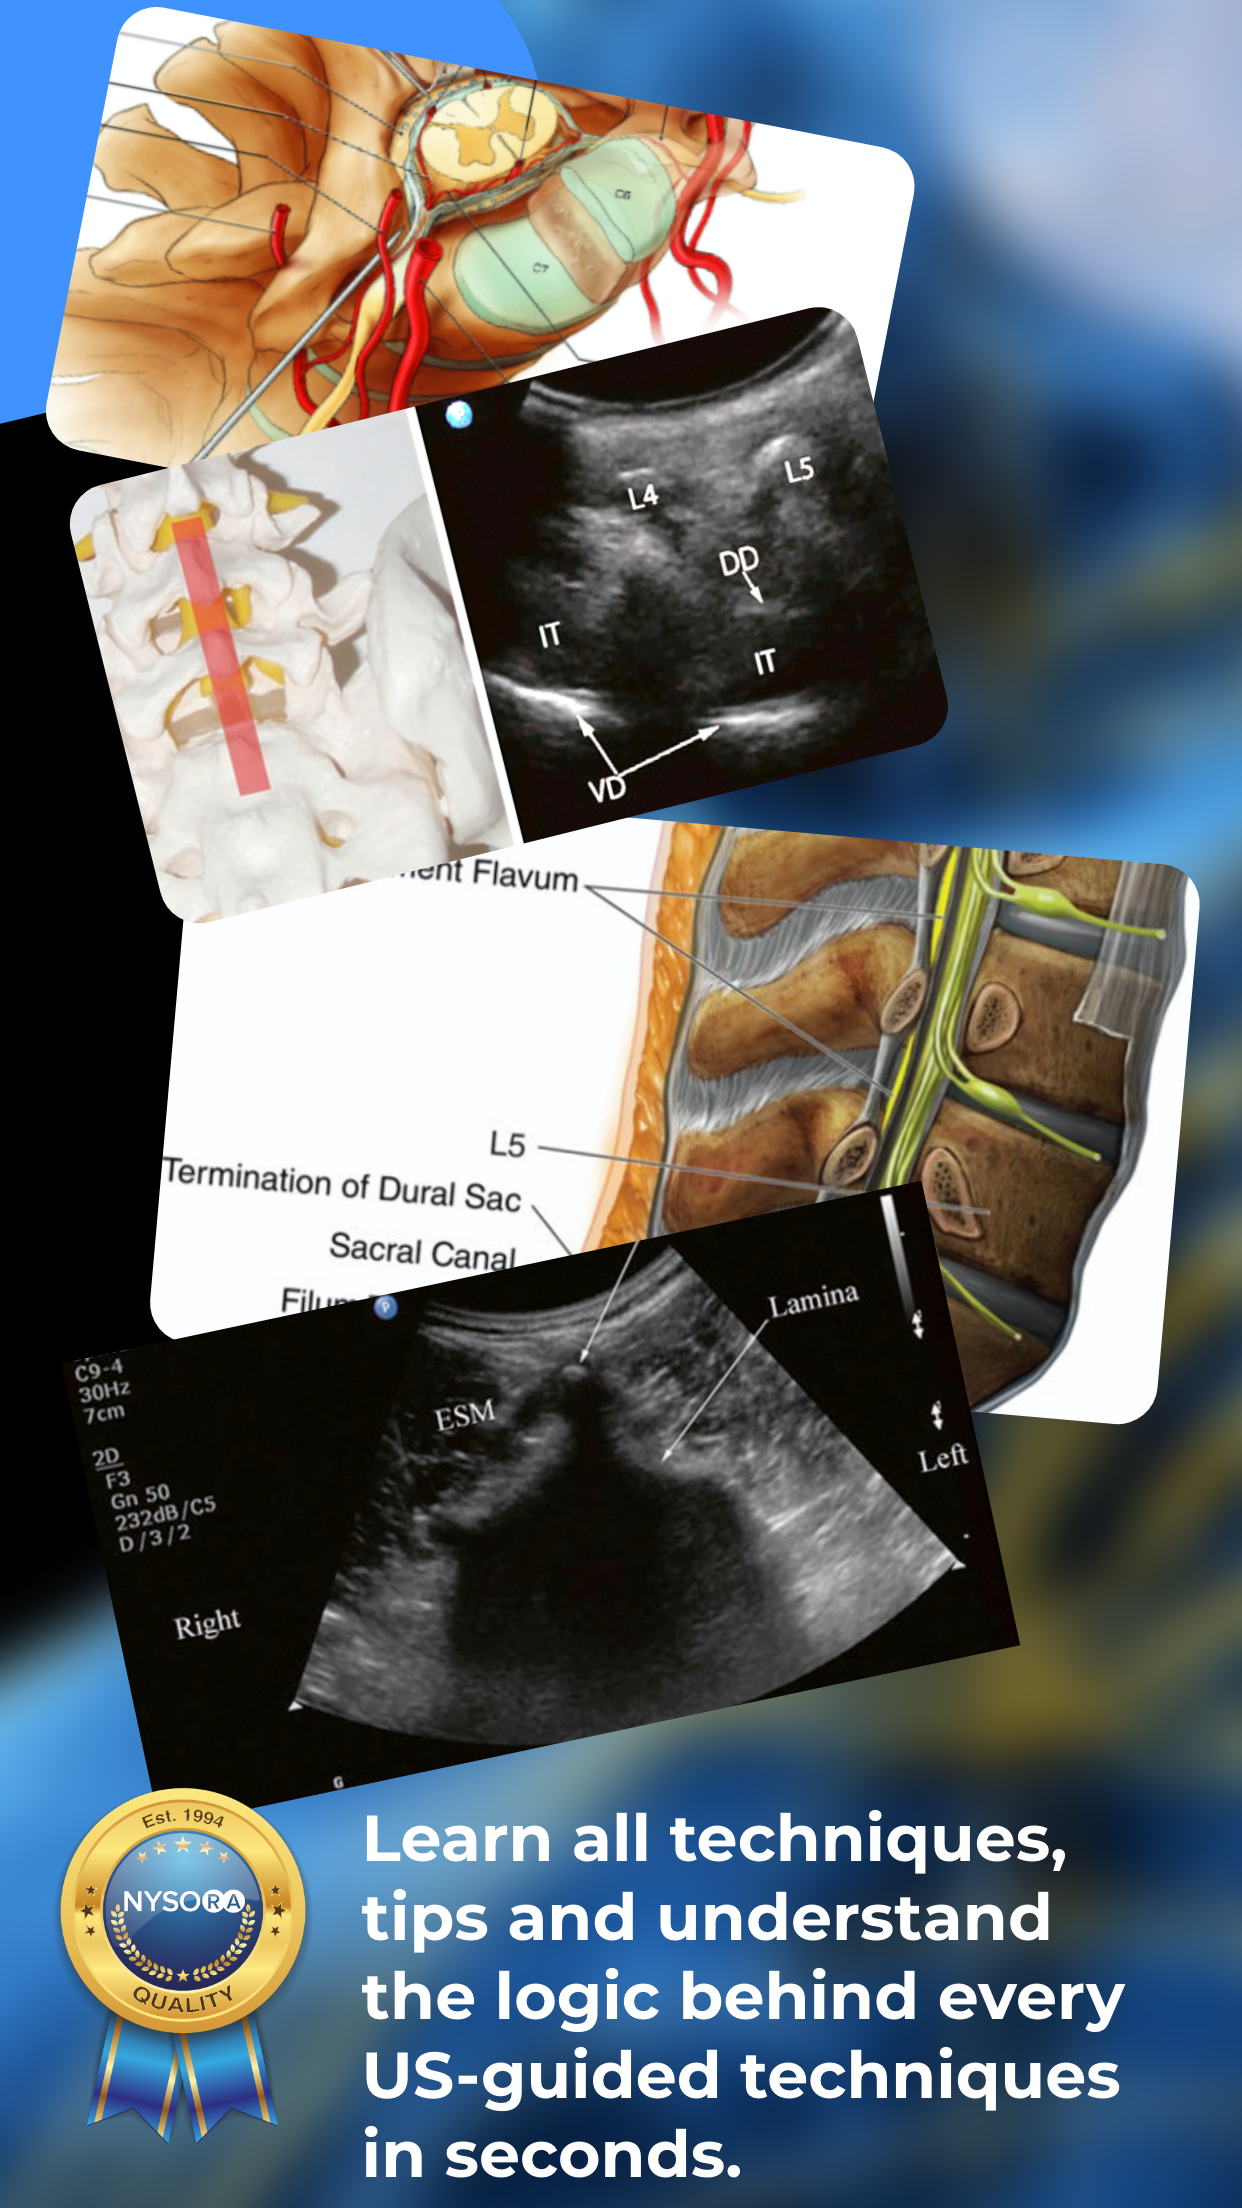

Published by the world’s leading authority on ultrasound, Dr. Samer Narouze. NYSORA Ultrasound-Guided Pain Blocks App describes the most practical and applicable techniques of ultrasound-guided pain medicine. Clear images, illustrations, ultrasound images, functional anatomy, and ultrasound-guided pain and MSK procedures; Loaded with practical clinical tips; Regularly enhanced by NYSORA’s illustrations and animations; Tips on how to get the best images; Ultrasound-guided: facet injections, median branch blocks, lumbar root injections, sacroiliac injection, celiac plexus block injection, blocks for pelvic pain, sympathetic block, stellate ganglion block, joint and bursa injections, knee injections, ultrasound-guided cervical discography, elbow, and shoulder bursa injections.